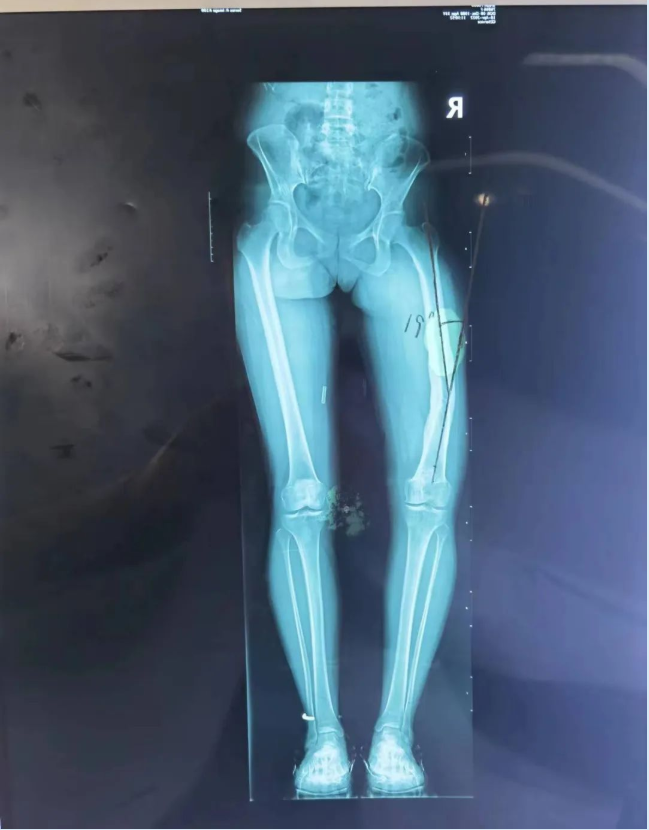

经接诊医师崔家平检查发现,患者右股骨畸形并功能障碍,右膝关节僵硬,不能活动;影像检查后发现右下肢前后及内外成角畸形明显,测量发现右侧股骨前后成角30度,内外成角19度,患者及家属急盼迅速治疗以缓解疼痛、矫正畸形。

(术前检查影像)